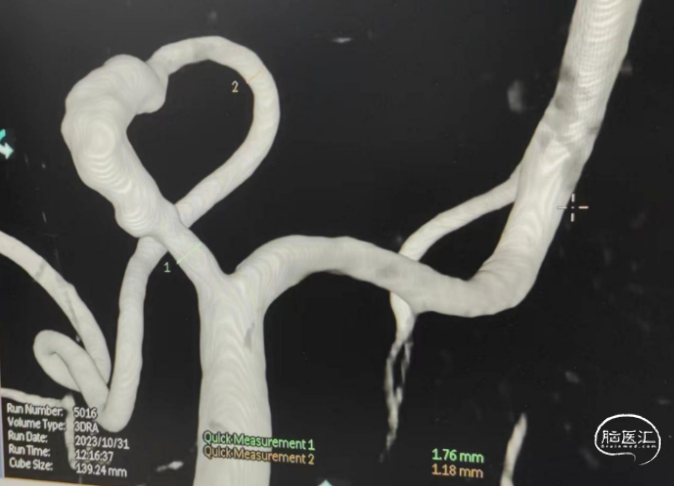

3、植入密网支架,优点是能有效保护夹层动脉瘤;缺点是载瘤动脉细小且弯曲通过TJMC18Plus微导管可能非常困难。幸运的是可供选择的密网支架规格齐全。决定选用方案3。

泰杰Nuva®血流导向密网支架TJED-D-2.5-20(预期血管直径和长度2.0mm*26mm)

全身肝素化,送入长鞘、中间管,在导丝指引下置入TJMC18Plus微导管。

术后造影见支架打开好、贴壁好,动脉瘤内可见造影剂滞留。